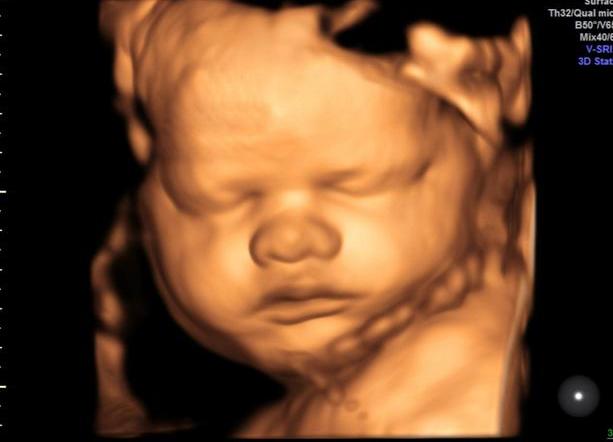

4.“嚎啕孕妈”火了,看到胎儿四维彩照被丑哭,娃没出生就惨遭嫌弃

半个月前,安徽合肥一位“嚎啕孕妈”火了!

这位孕妈满怀期待地去医院做四维彩超,可是当她看到胎儿的四维彩照后,泪如雨下,出了医院也是边走边哭边嚎啕:

“太丑了!没见过那么丑的小孩!”

原来,这位孕妈嚎啕大哭不是因为胎儿有问题,而是觉得胎儿太丑了……那么,能有多丑呢?

嗯……虽然这位胎儿谈不上漂亮,但是也不至于被丑哭吧?只能说这位孕妈过于期待了,所以才会过于失望!

网友看到这条消息后,也是纷纷调侃:

“可怜的娃没出生就惨遭嫌弃啊!”

各位家长,你们觉得这位胎儿丑吗?